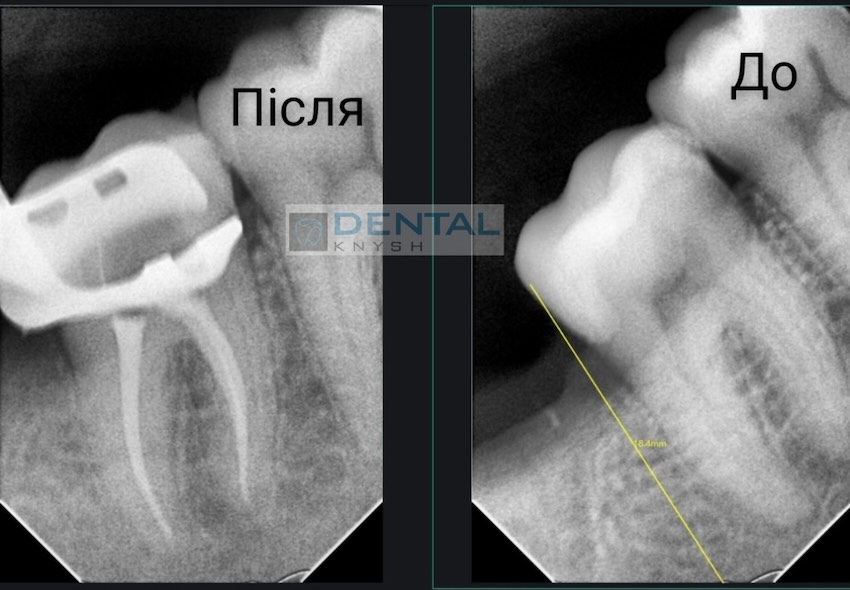

Лікар-ендодонтист Вадим Петриченко спеціалізується на лікуванні зубних каналів під мікроскопом.

Фото звіти

Більше фото звітів можна подивитися на сторінці Лікування зубів під мікроскопом